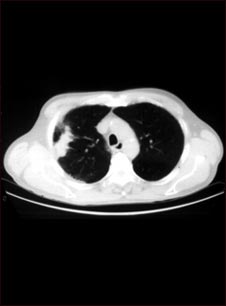

Tomografía computarizada del pulmón con cáncer de células escamosas

Esta tomografía computarizada muestra un corte transversal de los pulmones de una persona con cáncer pulmonar. Las dos áreas oscuras en el centro de la pantalla son los pulmones y las áreas claras en el pulmón derecho representan el cáncer (lado izquierdo de la imagen).